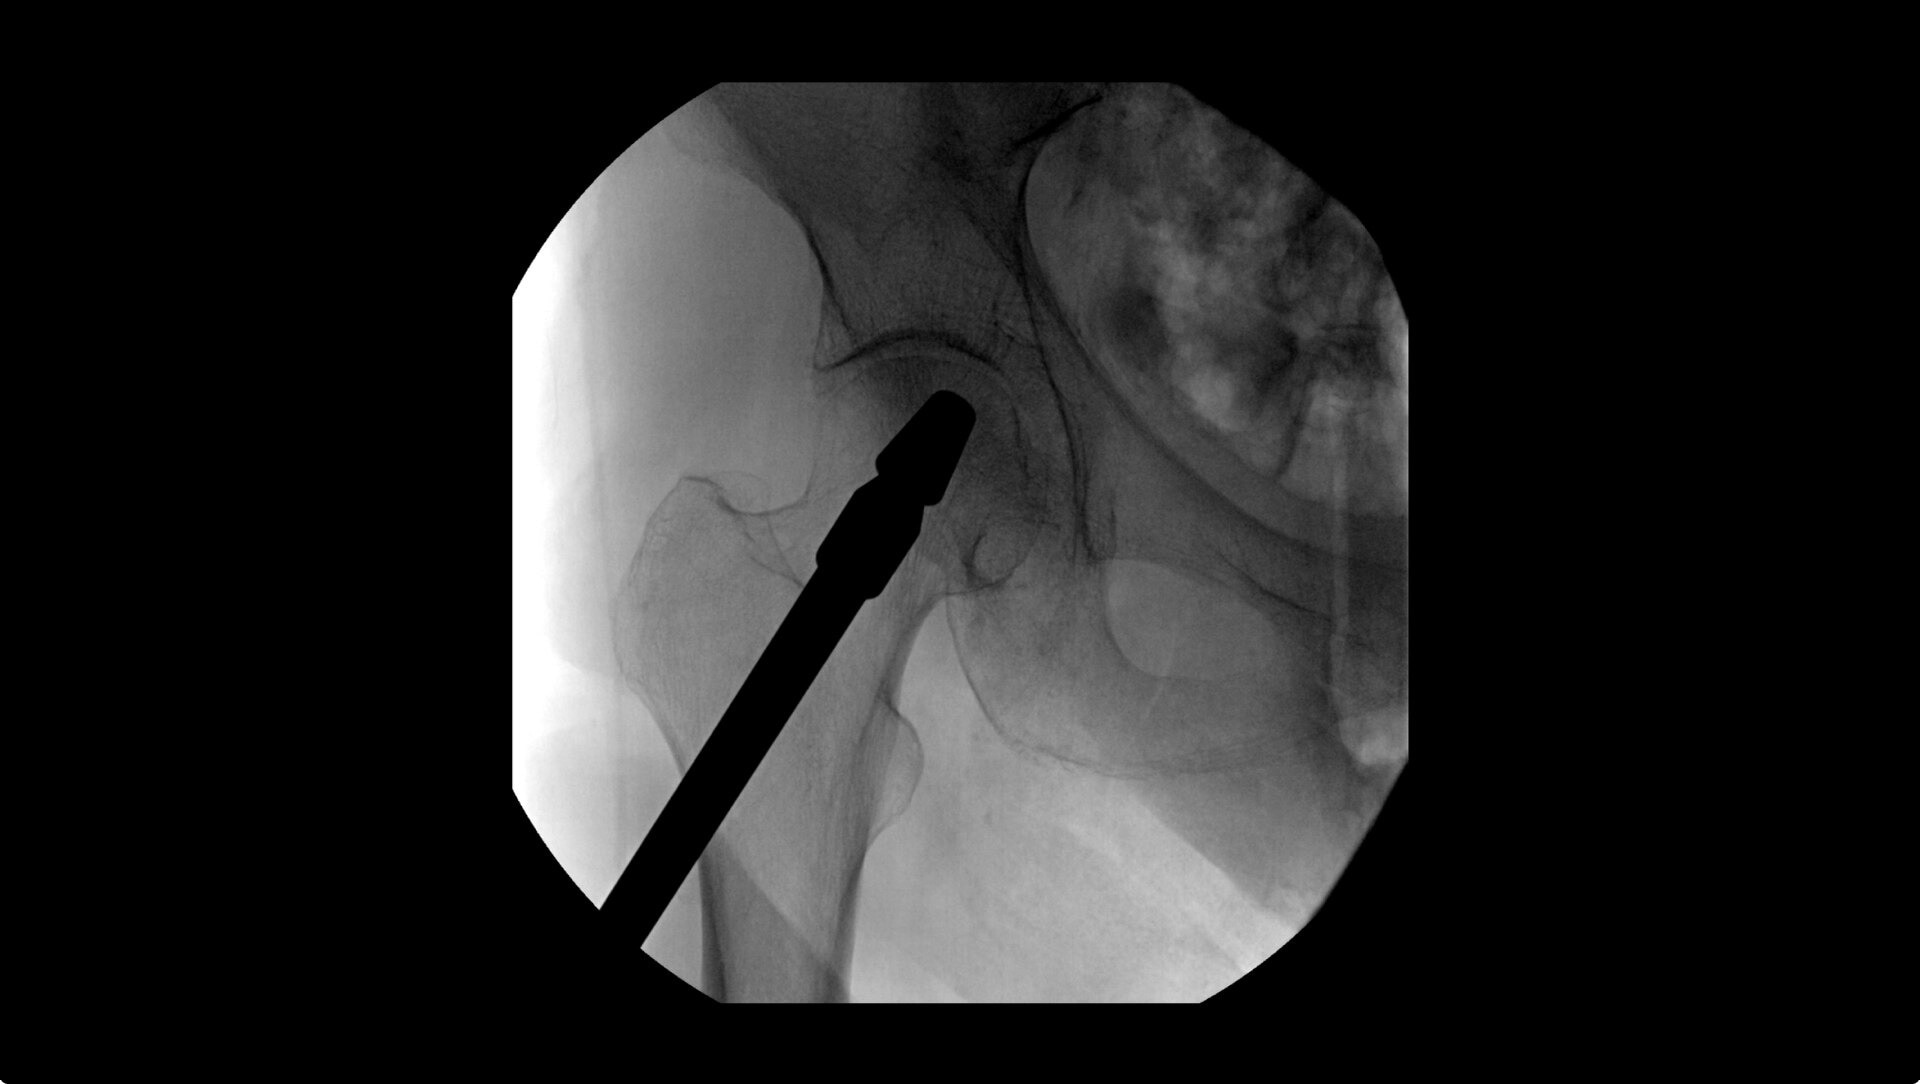

Mark right on the image displayed with Digital Pen, to template femoral and acetabular procedures and utilize measurement and angle tools for adding references for surgical planning.

Live Zoom up to 4X during a fluoro without the additional dose of Mag modes to assess orthopedic fractures and fixations.

During hip or femur imaging, capture up to 22% more Field of View by positioning detector closer to patient anatomy with the OEC low-profile X-ray tube housing compared to mono-block C-arms.

Complex orthopedic procedures require powerful imaging systems. OEC premium C-arms perform in a variety of procedures such as:

• Hip fracture fixation

• Hip replacement